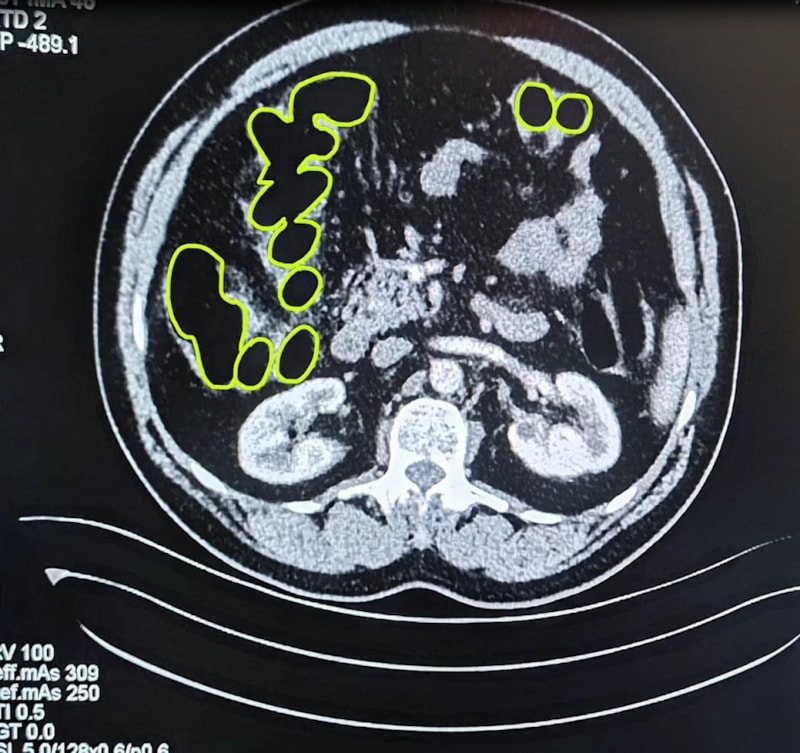

Röntgenlerinde midelerinde uyuşturucu madde olduğu belirlenen zanlılardan 20 gram çeşitli uyuşturucu madde ile 117 uyuşturucu hap ele geçirildi.